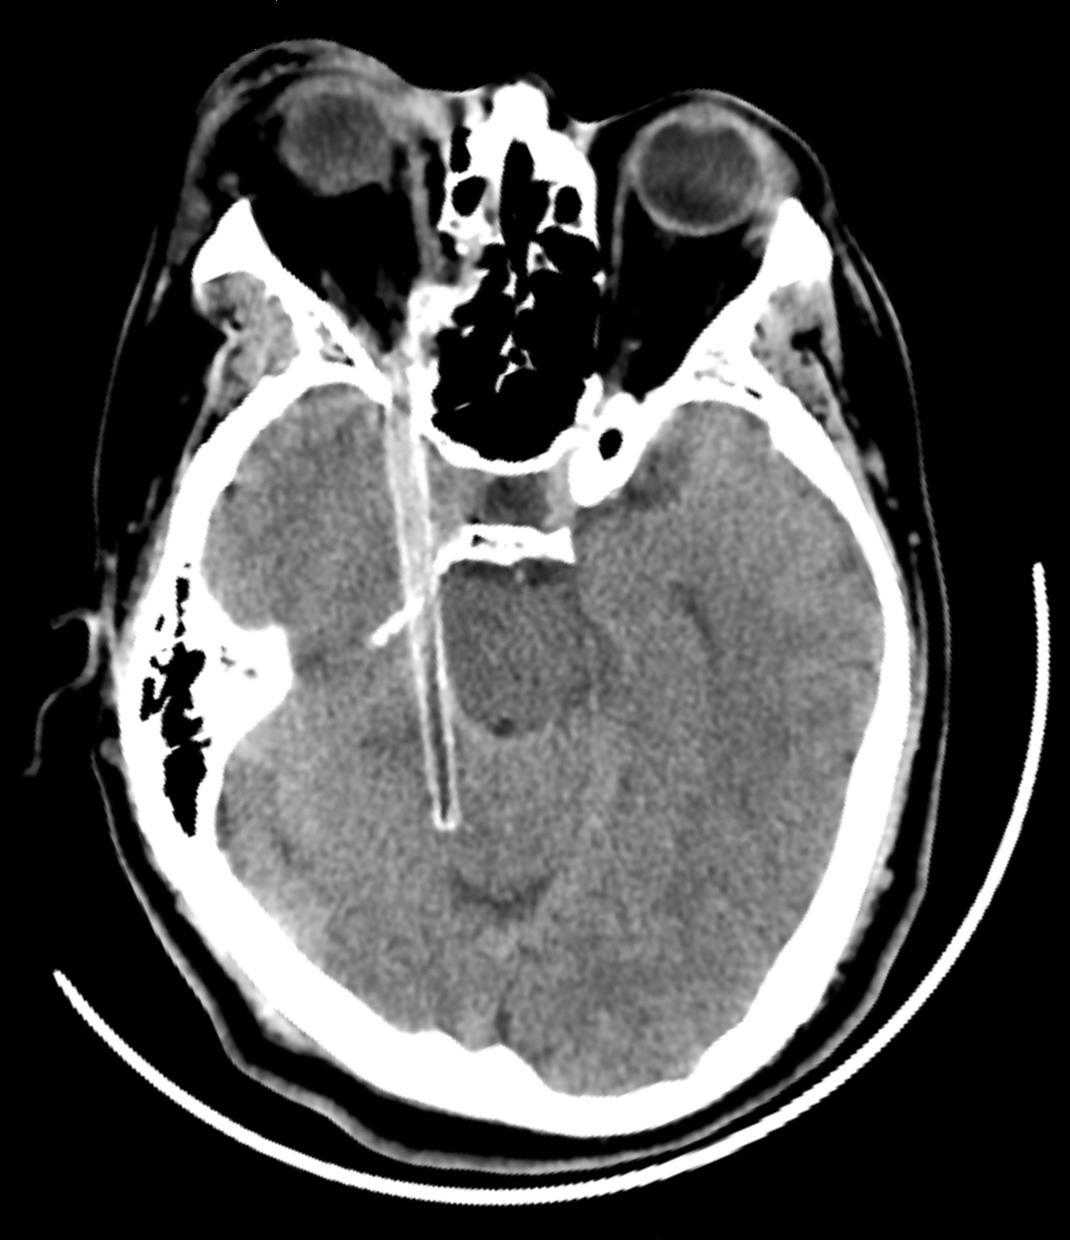

眶内眼球外异物致视神经损伤2例

关键词: 法医学, 视神经损伤, 颅脑损伤, 眶内眼球外异物, 视力下降